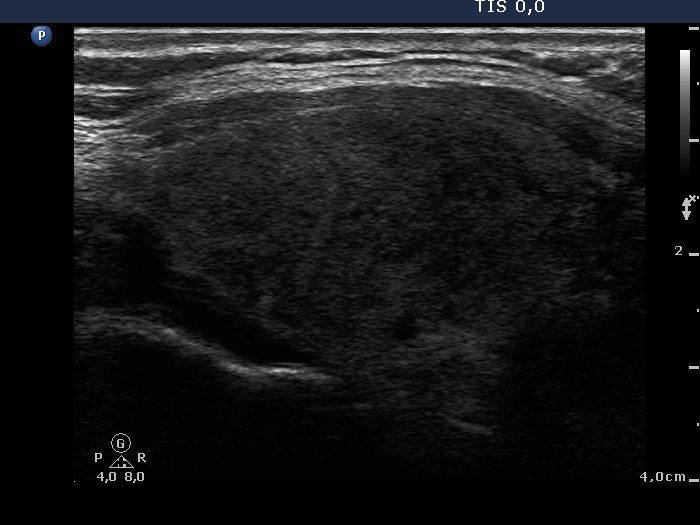

Ultrasonography: There were many hypoechogenic areas with blurred borders within both lobes. The vascularization was decreased.